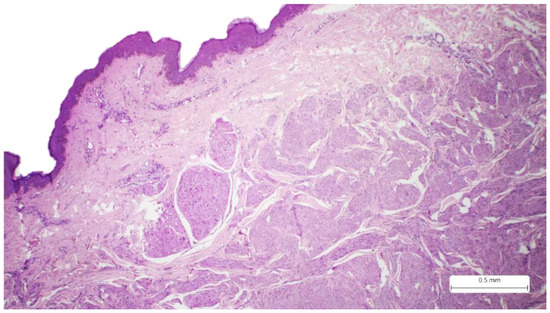

2. Case Report